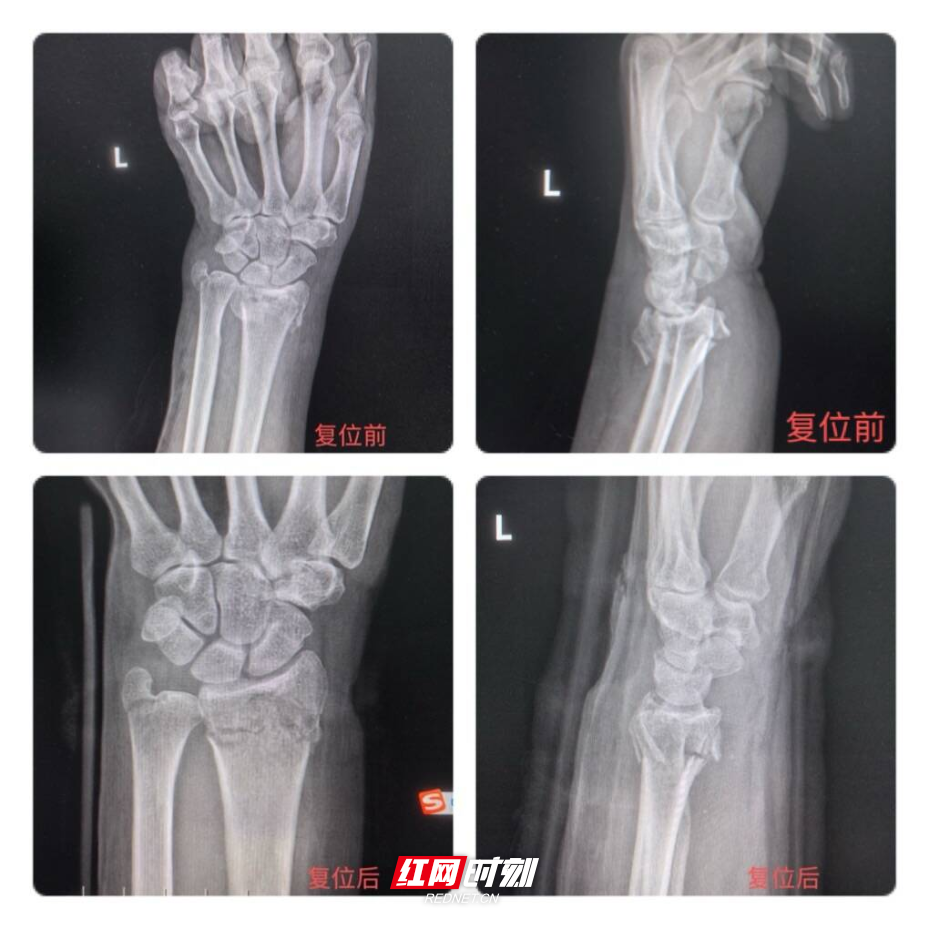

60多岁刘女士(化名)在家中不慎滑倒,手掌撑地后当即出现右腕剧烈疼痛、肿胀畸形、活动受限,家人紧急送医。周炀在接诊后,凭借丰富临床经验与娴熟正骨技术,快速为患者开展救治。经查体与影像学检查,确诊为桡骨远端科雷氏骨折,骨折端明显移位,需尽快复位固定。考虑患者为中老年女性,骨质疏松、对手术创伤耐受度较低,周炀结合病情量身制定中西医结合保守治疗方案,在充分安抚患者紧张情绪后,迅速开展精准手法复位。

复位过程中,周炀稳准发力,通过拔伸牵引、折顶对位、端提挤按等传统正骨手法,一气呵成完成骨折端复位,即时纠正腕部畸形。复位成功后,予医院特色中药外敷消肿止痛、活血化瘀,配合规范外固定与制动保护,全程创伤小、痛苦轻、耗时短。患者疼痛明显缓解,对治疗效果十分满意,连连感谢医护人员在除夕夜放弃团圆、及时救治与贴心照料。